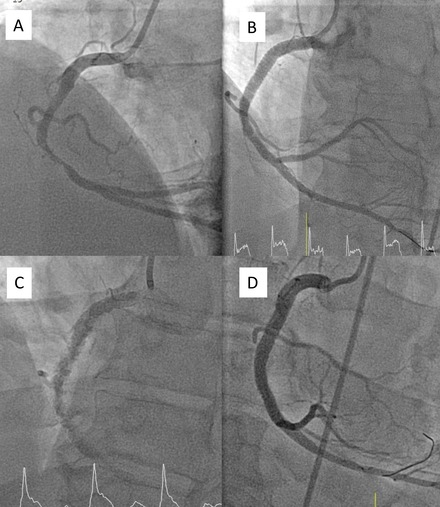

He was started on aspirin and heparin and taken emergently to the cardiac catheterization lab, where he received a loading dose of clopidogrel. Coronary angiography showed a 95% mid-right coronary artery stenosis due to an ulcerated plaque (Figure 2A). Three drug-eluting stents were placed, restoring TIMI grade III flow (Figure 2B). Forty minutes later, he developed sudden altered mental status and was found pulseless with ventricular fibrillation on telemetry. Return of spontaneous circulation followed resuscitation. Repeat angiography revealed acute in-stent thrombosis (Figure 2C). He underwent aspiration thrombectomy and repeat percutaneous coronary intervention, and was started on intravenous cangrelor. The next morning, clopidogrel was switched to ticagrelor for enhanced antiplatelet effect. The patient stabilized, and ponatinib was discontinued.